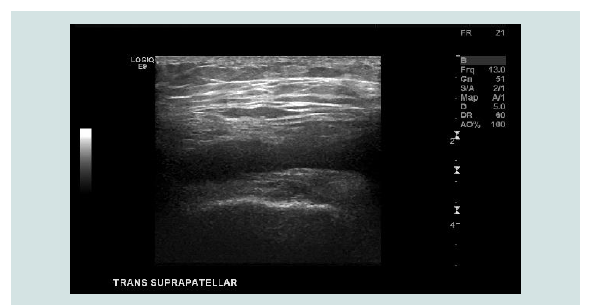

surrounding the knee (Figure 1). Ultrasound of the left knee

showed a small fluid collection of the medical knee, which appears

to be consolidated (Figure 2). She underwent ultrasound-guided

Figure 2: Ultrasound of the left knee showing a small fluid collection of the

medical knee, which appears to be consolidated.